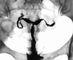

Туберкулезный папиллит может проявляться болями в поясничной области, почечной коликой, гематурией. Характерны «асептическая» лейкоцитурия, эритроцитурия и протеинурия. У больных, которые в прошлом лечились противотуберкулезными средствами по поводу туберкулеза других локализаций, микобактерии туберкулеза при бактериологическом и биологическом исследовании мочи могут не обнаруживаться. При рентгеноконтрастном исследовании верхних мочевых путей (экскреторной урографии или ретроградной пиелографии) выявляют небольшие дополнительные тени в области свода одной или нескольких почечных чашек, в более поздних стадиях — деструктивный процесс в почечных чашках (рис. 7), сопровождающийся стенозом или рубцеванием их шеек. В отличие от папиллитов нетуберкулезной этиологии, главной особенностью которых является постоянство урографической картины на протяжении длительного периода наблюдения, для туберкулезного папиллита характерна положительная или отрицательная урографическая динамика.

При кавернозном туберкулезе почек субъективные симптомы те же, что и при туберкулезном папиллите. Выявляют пиурию, микобактерии туберкулеза в моче (при бактериоскопии, культуральном и биологическом исследовании). При экскреторной урографии или ретроградной пиелографии (рис. 8) обнаруживают рентгенологические признаки разрушения почечного сосочка либо каверну в мозговом веществе почки, не сообщающуюся или сообщающуюся свищевым ходом с чашечно-лоханочной системой. Обтурация или облитерация просвета шеек почечных чашек или мочеточника сопровождаются болями в поясничной области, иногда почечной коликой, рентгенологически характеризуются прогрессированием ретенционных изменений вплоть до гидронефротической трансформации почки с резким подавлением ее функции.